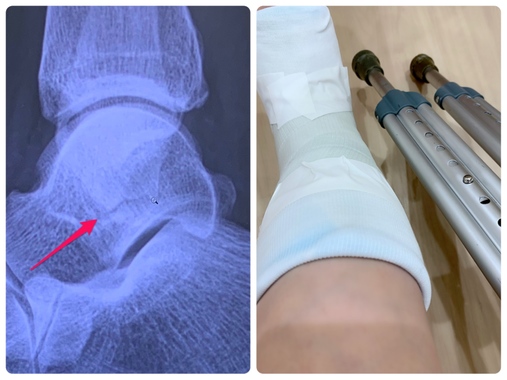

外科的な病気は、その時、生活が不便になりますね・・・手足の指先や、鎖骨って、結構簡単に折れます・・・レントゲン見せられると衝撃を受けます(うわ・・・折れてる・・・粉砕している・・・みたいな感じ)

患部の写真がとっても痛々しい・・・。

先生曰く、あの「パキッ!」は ヒビが入った音だったようですw

wzjmさんの骨折は ホントに大変だと思いますが、私は全然大したことないんです。これマジで…(^^ゞ

ヒビが入ってると言われた時にギプスは覚悟してたのですが、処置室に入ると先生が何やら水道の所でゴソゴソしてました。

その濡らした物体をタオルにくるみ、私のところへ来ると「固定せなアカンから…」と言いながら、その物体を広げ 私の足に。

その手さばきは、まるで素人のようにぎこちなく、初めて使うのが私にも分かるほどでした(^^ゞ

内心「大丈夫かいな…」と思っていると、ようやく巻き終えた包帯をテープで止めた瞬間、、「あっ!これ逆やな…」(ーー;)

そう、裏表 逆にしてたんですw

慌てて外そうとしたのですが、時すでに遅し。。

看護師さんが「もう固まってますよ。新しいのにした方が早いでしょ」と、新しい(物体が入った)箱を開け 再度チャレンジ!

今度は何とか無事に?装着できました。

画像で分かるかもですが、包帯の巻き方もグチャグチャw

その後、レントゲンを見せてもらいながら話してたんですが、私が「靭帯が切れたのかと…」と言うと、「靭帯も切れてるかも知れんけど、分からんなぁ」と軽く流されました。

切れてるかもって、、分からんって、、大丈夫かいな?

やっぱり別の病院で診てもらった方がいいのかな~と思っていると「明日も診せに来て」と言われたので、とりあえず行って来ます💧

昨夜 足首の骨折について ググりまくり、色んな症例を見ていると…

最初の固定が大事!とか、しっかり治療しないと捻挫しやすくなったり 年を取ってから関節がゆるくなるとか不安なことばかり書いてたので、今日 仕事終わりで別の整形外科に行って来たんです(^^ゞ

これまで流れを説明して、、レントゲン撮影から仕切り直し。

(もっと分かりやすいレントゲンがあったんだけど、ギプス巻くのに呼ばれちゃったから撮れず…)

先生「折れてるやん…」

ヒビちゃうんか~いっ!!(>_<)

年配の人なら ギプスをせずに軽く固定する程度で済ませることもあるらしいけど、まだ若いから 骨をしっかりくっ付けておいた方がいいとの事で、全体を覆うギプスを巻くことになりました。

で、当然ながら 松葉杖を渡される訳ですが、、

前の病院で貸してもらったものよりも、持ち手部分のクッション性が高くて 手のひら痛がマシだったんです♪(これなら我慢できるかも…w)

今回の病院は、大きな病院の整形外科で勤務されてた先生が 2年前に開業した新しい病院だったので、建物も設備もピカピカ☆彡

クチコミの評判に「症状の説明が丁寧」と書かれてた通り、しっかりと説明してくださり、ギプスをしてる間に気を付けることなども教えてもらえたのですが、よくよく考えると前の先生からは そういう話は何も聞かされなかったなぁ~と。

「ヒビ入ってるから固定せな…」しか言われなかったような…w

ヒビ=骨折です...(>_<)

私が骨折した部位は 折れた際に骨が横にズレてしまうケースも多いらしく、そうなると手術が必要だったので、それを思えば軽傷ですが・・